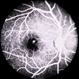

- Giant Retinal Tear

- giant retinal tear, idiopathic

- Fundus photograph of a 40-year-old man who presented with a history of progressive inferior visual field defect in the right eye over 2-3 weeks.